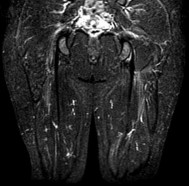

A 24-year-old collegiate hockey player presents with persistent anterior groin pain exacerbated by hip flexion and internal rotation. Radiographs demonstrate an alpha angle of 72 degrees on the Dunn view. Which of the following best describes the primary pathomechanical pattern of chondral damage associated with this morphology?

An alpha angle > 55 degrees indicates Cam-type femoroacetabular impingement (FAI). Cam morphology causes outside-in shear forces against the anterosuperior acetabular rim during hip flexion and internal rotation. This selectively damages the transitional zone cartilage, causing delamination of the articular cartilage off the subchondral bone while often leaving the labrum initially intact. Pincer impingement typically causes labral crushing and contrecoup chondral lesions.